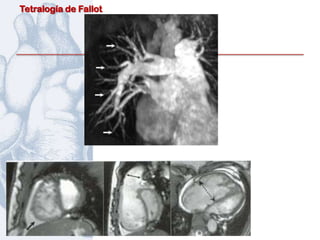

Otros estudios :

Resonancia Magnética Nuclear

Resonancia Magnética

Volumen final

de la diástole     Fracción

y sístole del   expulsión VD

VD ajustado

SC

Seguimiento:

cada 2 años